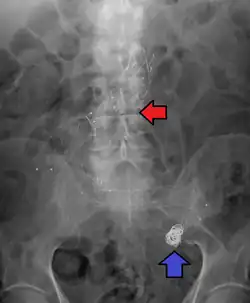

Abdominal aortic aneurysms are commonly divided according to their size and symptomatology. An aneurysm is usually defined as an outer aortic diameter over 3 cm (normal diameter of the aorta is around 2 cm),[17] or more than 50% of normal diameter that of a healthy individual of the same sex and age.[9][18] If the outer diameter exceeds 5.5 cm, the aneurysm is considered to be large.[16]

Abdominal aortic aneurysm involves a regional dilation of the aorta and is diagnosed using ultrasonography, computed tomography, or magnetic resonance imaging. A segment of the aorta that is found to be greater than 50% larger than that of a healthy individual of the same sex and age is considered aneurysmal.[9] Abdominal aneurysms are usually asymptomatic but in rare cases can cause lower back pain or lower limb ischemia.